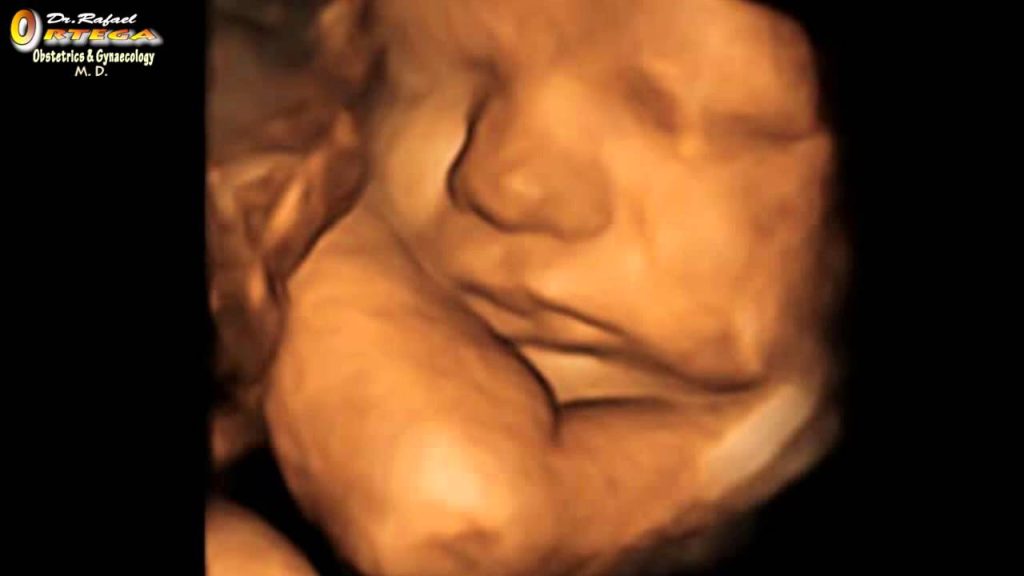

The title of Dr. Michael McCutchen’s intriguing column is “Drop the euphemisms and get uncomfortable when talking about abortion”. We can understand why the forces of darkness employ a steady diet of doublespeak. Euphemism are handy shields to ward off a confrontation—in the case of abortion— with its bloody, unforgiving, and pitiless reality.

No wonder pro-abortionists have worked for 60+ years to elevate euphemisms to an art form. The truth must be avoided at all costs.